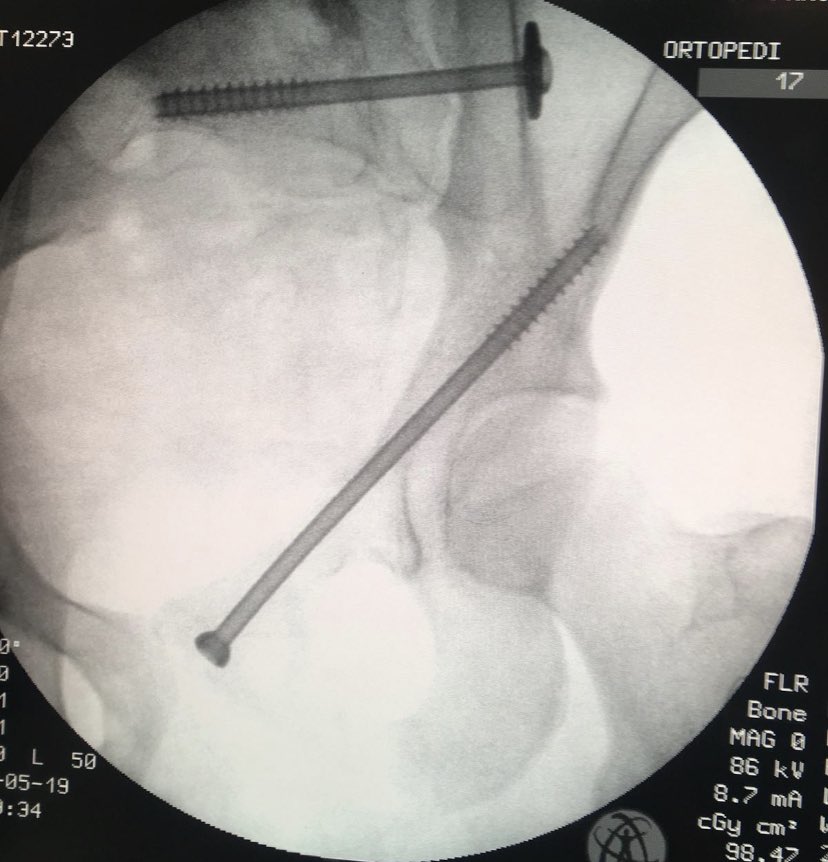

Percutaneous acetabular fixation

Dr. Diego López tweet mediaDr. Diego López tweet mediaDr. Diego López tweet media

@suhirad Yes of course! But with good bone, non conminution neither displacement and component tranverse AC fx with SIj fixed, i feel good not to open ischium or lateral window